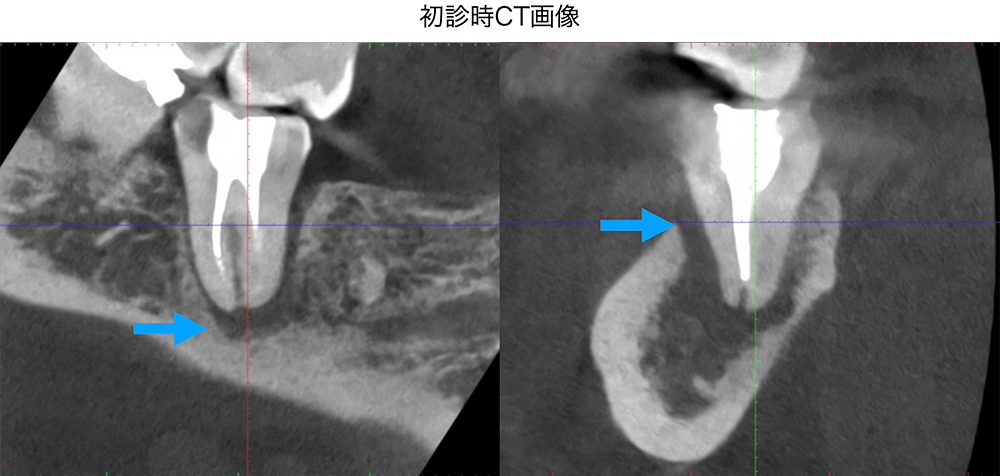

金山デンタルクリニックでは、治療の前に必ずCT撮影を行い、神経の本数や根の形、病変の大きさを正確に診査。治療の可能性や成功率まで含め、CTの画像を見せながら丁寧にご説明しています。治療後の経過もマイクロスコープやCT画像をお見せしながら、ご説明させていただきます。